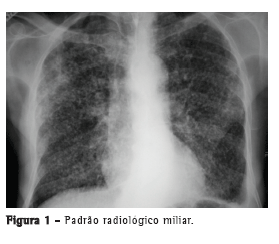

Com relação aos achados radiológicos, infiltrados reticulares e consolidação são os padrões mais frequentes,(5,6,10,15,17) sendo que cavitação pode estar presente em 27-50% dos casos.(6,10,16) As Figuras 1 a 4 mostram alguns dos principais padrões radiológicos nesse contexto.